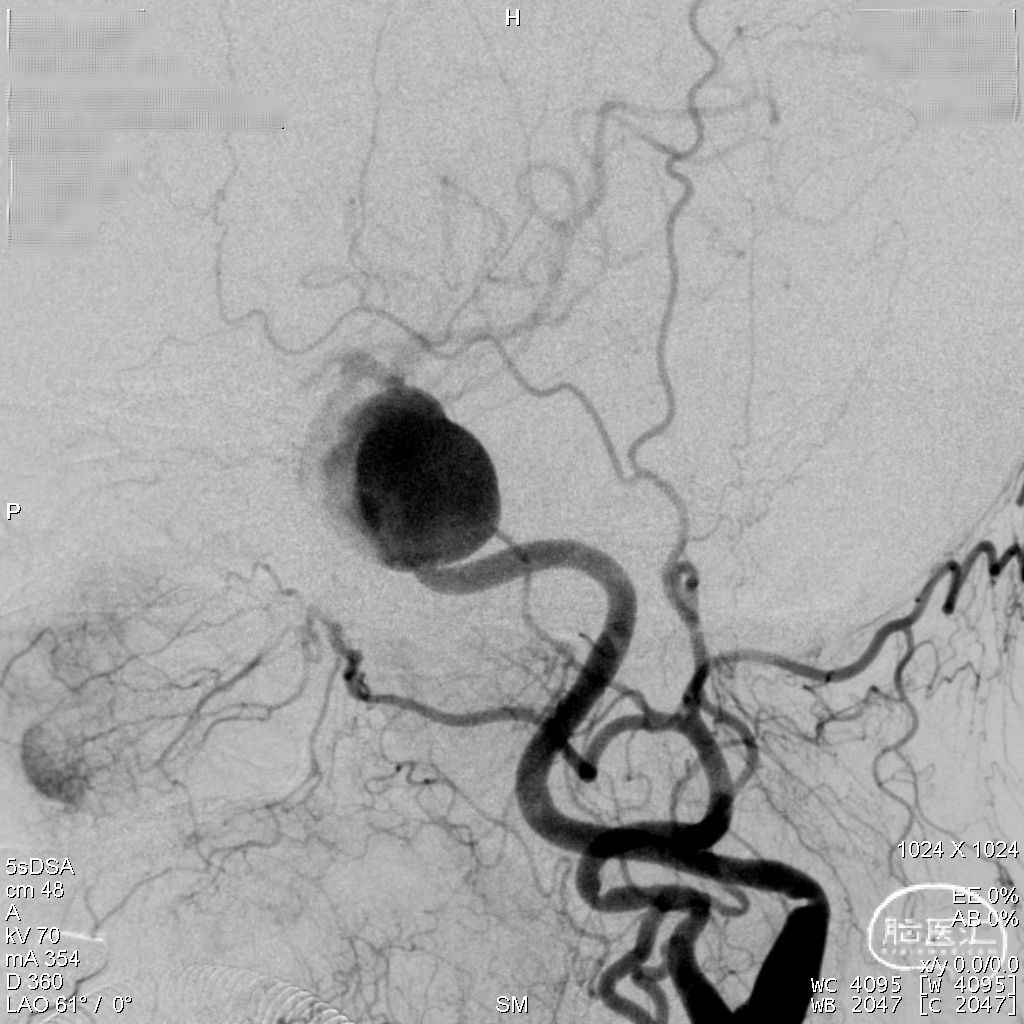

DSA造影显示为左侧颈内动脉海绵窦段巨大动脉瘤。

通过3D工作位测量出左侧海绵窦段动脉瘤尺寸:33mm不规则动脉瘤,载瘤动脉尺寸:近端直径4.55mm,远端直径3.97mm。

造影后发现该患者左侧海绵窦段动脉瘤,动脉瘤不规则,最大径33mm,未破裂,不累及分叉部,动脉路径迂曲。